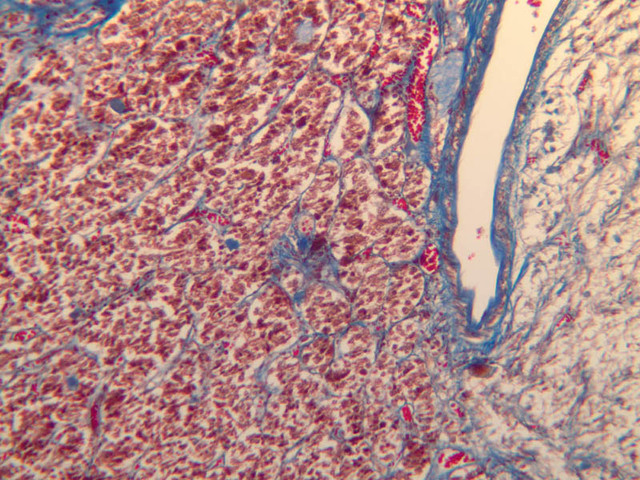

The adrenal gland (slide B-59, H&E [2.5x-labeled, 10x-labeled, 20x, 40x-labeled] [2.5x, 10x-labeled, 20x, 40x]; B-60, H&E [2.5x-labeled, 10x, 20x, 40x]; B-62, H&E [10x, 20x, 40x] [2.5x, 10x]) is a composite organ consisting of two functionally, structurally and embryologically different parts—an outer cortex and an inner medulla. Observe the gland at low power. Find the loosely organized tissue that comprises the medulla and the partially-separated columns of cells that make up the cortex. Scan the capsule and the tissue around it, looking for nerves and blood vessels. Study the pattern of cortical vasculature. In a pattern similar to that seen in the pars distalis of the pituitary, sinusoids run along the edges of columns or cords of cells. Owing to different arrangements of its constituent cells, the adrenal cortex has a layered appearance. From the capsule inward, these cortical layers are known as the zona glomerulosa, the zona fasciculata, and the zona reticularis.

The zona glomerulosa is located immediately beneath the capsule (B-60 adrenal gland, dog [10x, 20x] [20x, 40x]; B-59 [2.5x, 10x, 20x] [2.5x, 10x, 20x]). Its constituent cells are arranged in arcs or spheres, and, owing to their relatively small size, their nuclei appear to be close together. Cells of the zona glomerulosa secrete mineralocorticoids (e.g., aldosterone). The zona fasciculata consists of parallel columns or cords of cells that radiate toward the medulla and are separated by blood sinusoids (B-60 [2.5x, 10x, 20x, 40x]; B-62 [20x, 40x]). Owing to the extraction of lipids during histological processing, the cytoplasm of cells in the zona fasciculata appears highly vacuolated or "foamy". Cells of the zona fasciculata secrete glucocorticoids (e.g., hydrocortisone & cortisone) and some gonadocorticoids (weak androgens). The zona reticularis is the deepest cortical layer and lies adjacent to the medulla (B-60 [20x, 40x]; B-62 [20x, 40x]). It is characterized by irregular, interconnecting cords of cells which are separated by anastomosing capillary networks or sinusoids. Cells of the zona reticularis, which are smaller than those of zona fasciculata and do not contain as many lipid vacuoles, secrete gonadocorticoids and some glucocorticoids.

The medulla is composed of large epithelioid cells, arranged in small groups or cords which are separated by blood vessels. Usually, several large veins mark the center of the medulla. When fresh adrenal gland is incubated in solutions of chromium salts (as was the specimen on slide B-61), brownish precipitates form in the cells of the medulla-- hence, the name chromaffin cell (B-61, chromaffin [2.5x, 10x, 20x, 40x] [2.5x, 10x, 20x, 40x-labeled]). The more darkly stained chromaffin cells are known to contain norepinephrine, the less darkly stained cells, epinephrine. In essence, chromaffin cells are specialized postganglionic sympathetic neurons. How does the ultrastructure of these cells differ from that of the secretory cells of the adrenal cortex?